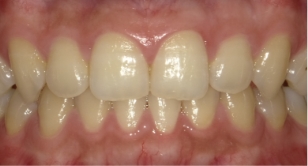

伊藤矯正歯科医院での安定した症例

これに対し伊藤矯正歯科医院では、抜歯を伴う矯正を行ったのちに何も装置を使用しなくて何年か経過しても、かなり安定している症例をみることが多くありました。(「安定調査症例1~4」と当HPの症例集ページ「叢生第3,4症例」をご覧下さい。)そこで治療が終わって数年経過した時点で、資料採得のできた14症例について歯並びの変化を観察しました。